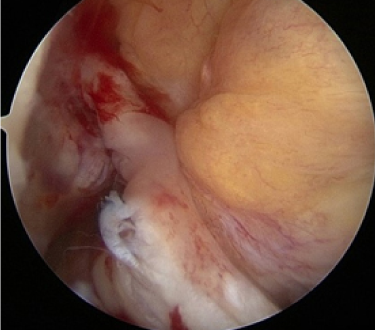

십자인대가 파열되어 하얗게 보임

2020.09.08

십자인대를 재건한 모습

2020.09.10